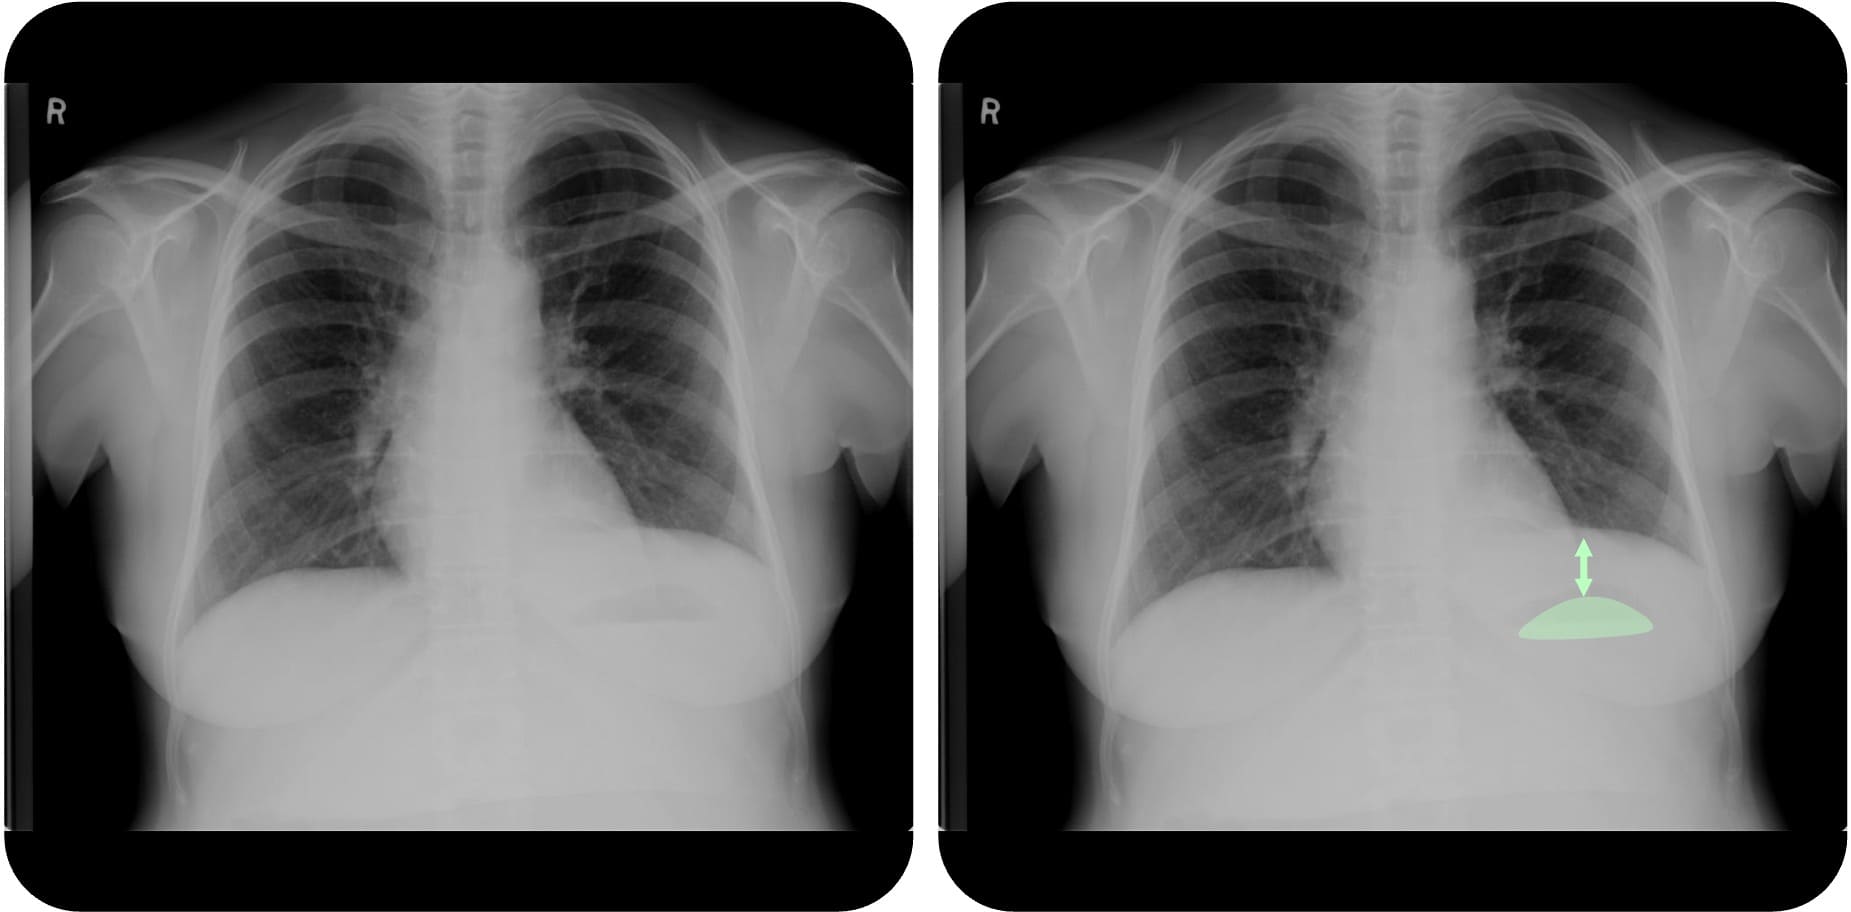

Subpulmonaler Erguss

Beim subpulmonalen Erguss sammelt sich die Flüssigkeit unterhalb des Lungenflügels zwischen Zwerchfell

Case courtesy of Nafisa Shakir Batta, Radiopaedia.org, rID: 24982

- Subpulmonaler Erguss: Pseudo-Zwerchfellhochstand